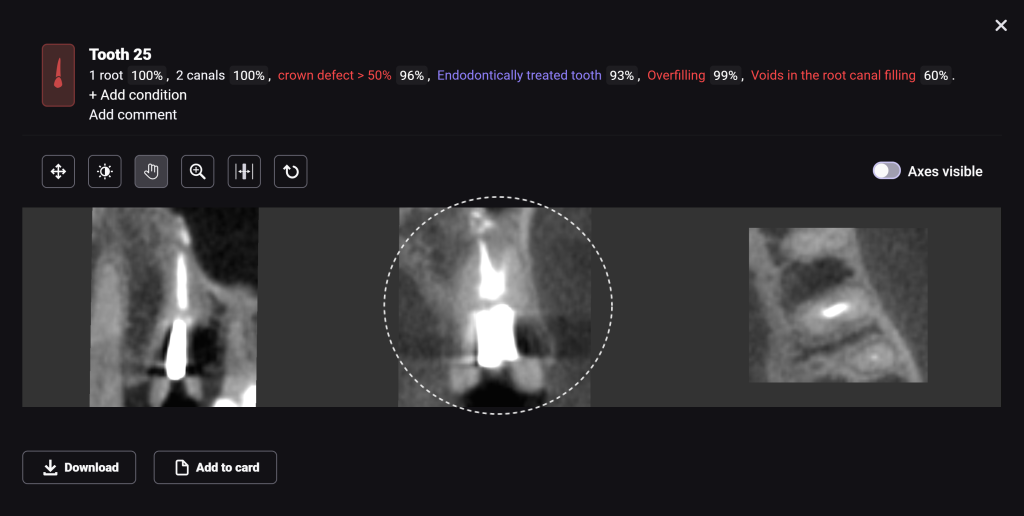

The planning of immediate implant placement using Diagnocat AI has many advantages for both the doctor and the patient. Let’s consider them using a clinical case example, in which the removal of tooth 25 (Universal 13) and subsequent implant placement were planned

In order to predict the prognosis of the tooth, data from the Diagnocat radiological report and visualization capabilities of the 3D-Viewer tool were utilized, in addition to a clinical examination